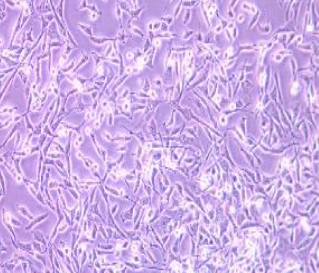

- 细胞形态:

上皮细胞样,贴壁生长

2) 形态:上皮细胞样,贴壁生长